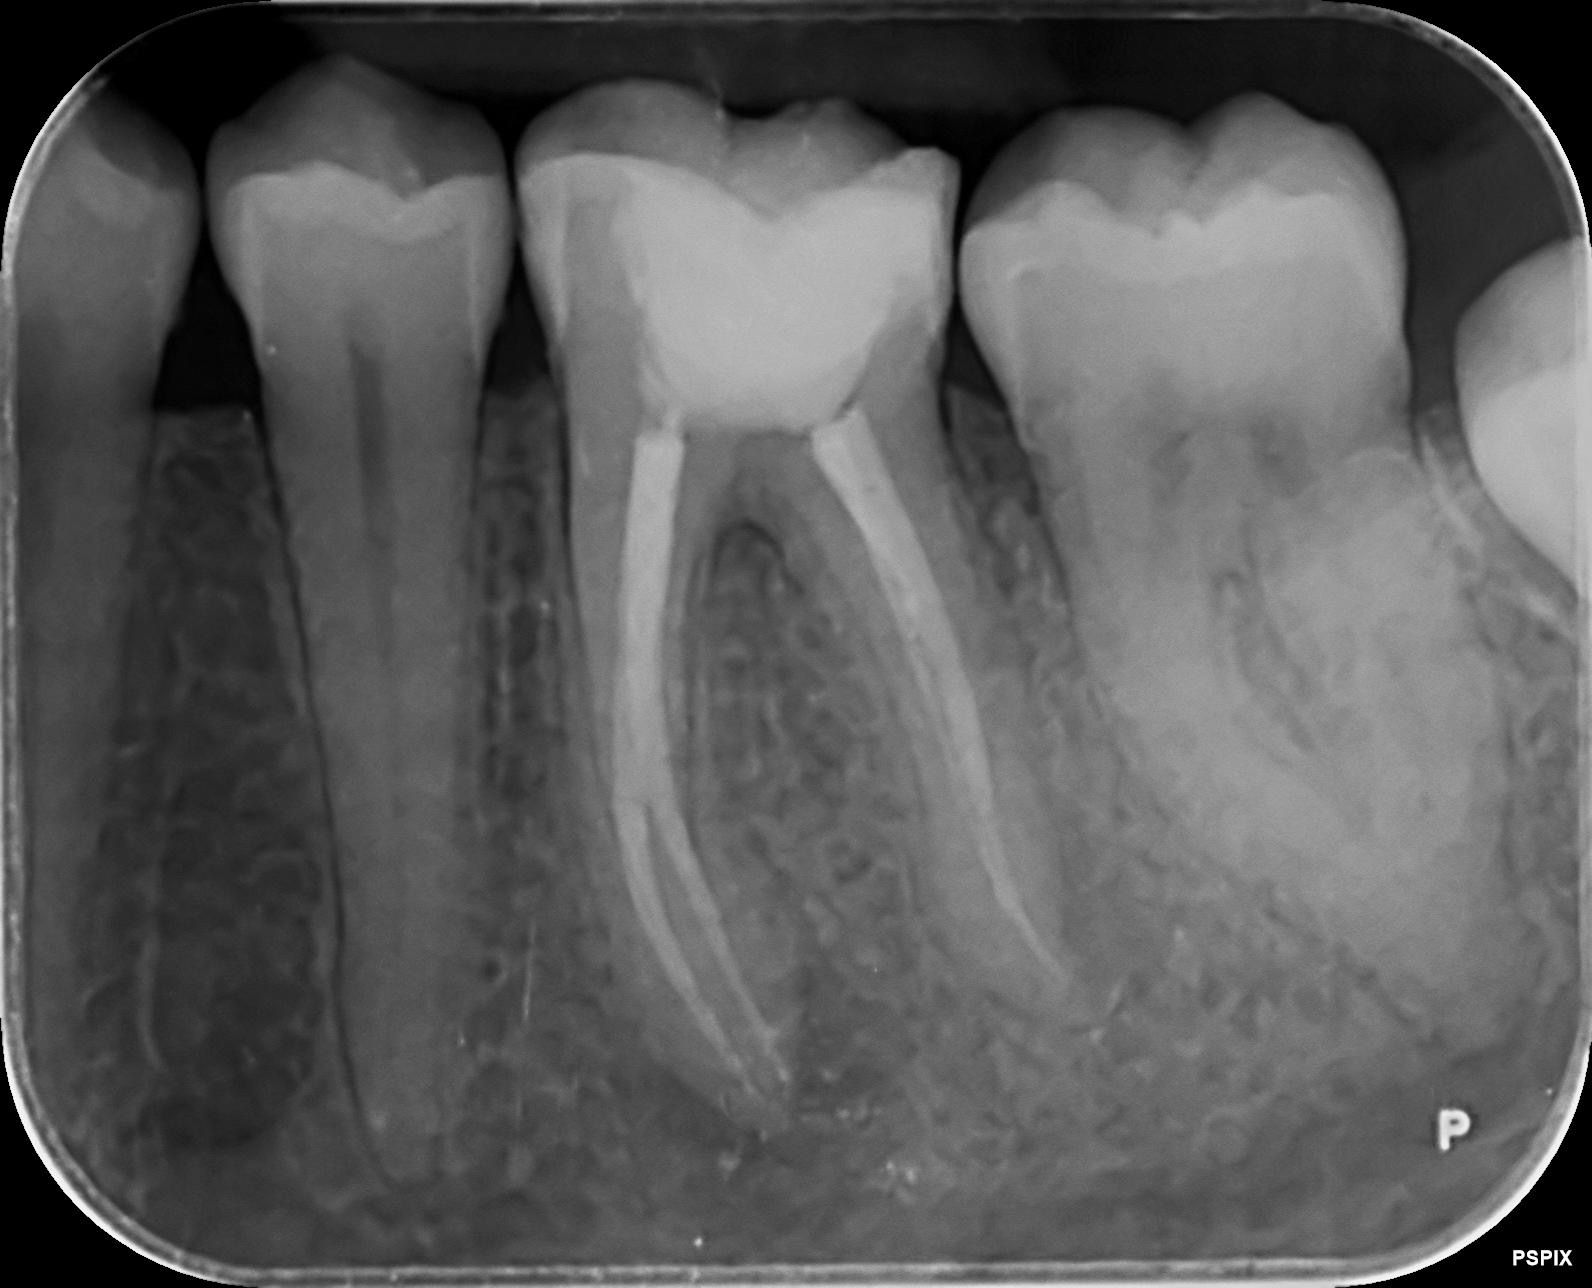

Déspues

Caso 1